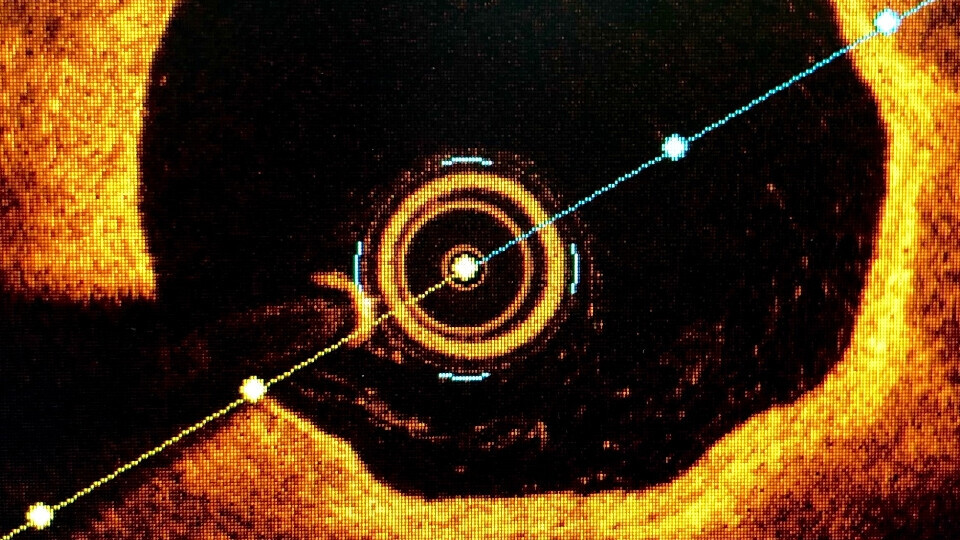

ESC-Kongress 2023 | Hot Line 4: ACC-Präsident Dr. B. Hadley Wilson fasst die Ergebnisse der Studien zu intravaskulärer Bildgebung im Vergleich zur Angiographie zusammen.

oct-intravaskulaere-bildgebung-shutterstock-2186368653-32zu9-1920x540